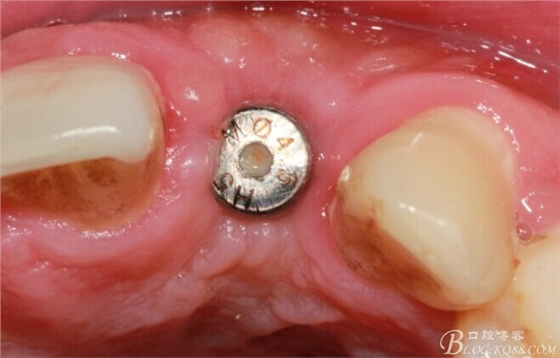

術(shù)后1個(gè)月。